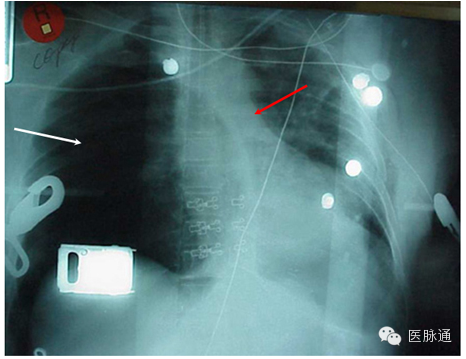

张力性气胸是指空气蓄积于胸膜腔内。当受损肺组织形成单向活瓣,造成空气只能进入而无法离开胸膜腔,即形成张力性气胸。应根据临床表现作出张力性气胸的诊断,包括气管向对侧移位,同侧叩诊过清音,同侧呼吸音降低,颈静脉充盈以及低灌注。典型的X线表现包括同侧肺塌陷(图3白色箭头)伴肋间隙增宽,以及纵隔向对侧移位(图3红色箭头)。若张力性气胸发生于左侧,则左侧膈肌下降,但若发生于右侧,则肝脏可限制膈肌的下降。

图3